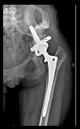

The radiological examination allowed us to verify the close bone-to-implant contact and the unchanged position of the implant during follow-up.

In all the cases operated with the above-described targeting procedure, the stems of the cups remained between the cortical bone surfaces without perforation of the linea terminalis, as shown by postoperative radiographs. There were no complicated surgical situations. In 16 cases, the wound healings were uneventful, and the hips were able to bear weight again after postoperative rehabilitation.